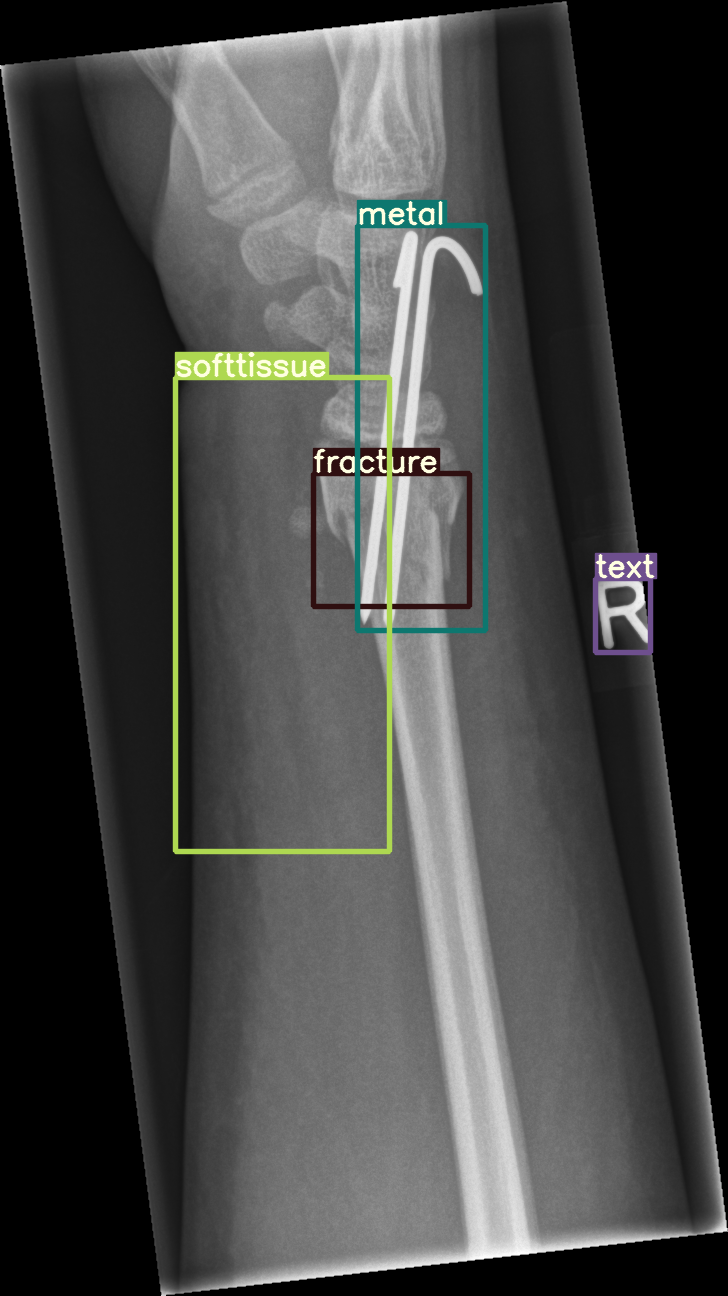

Figure 8: Sample of five images from the GRAZPEDWRI-DX test set, displaying ground-truth and predicted bounding box annotations: (a-e): ground-truth annotations, (f-j): YOLOv11l annotations, and (k-o): G-YOLOv11 annotations.

Table 4: Confidence scores predicted by YOLOv11l and the proposed G-YOLOv11l detectors for five images from the GRAZPEDWRI-DX test set, PR: pronator sign, FP: False positive.

Figure number Class name Confidence score predicted Confidence score predicted

by YOLOv11l by our G-YOLOv11l

8(a) soft tissue, fracture, metal, text -, 0.670.670.670.67, 0.860.860.860.86, 0.830.830.830.83 -, 0.700.700.700.70, 0.890.890.890.89, 0.840.840.840.84

8(b) fracture, text 0.780.780.780.78, 0.710.710.710.71 0.790.790.790.79, 0.730.730.730.73

8(c) fracture, text 0.820.820.820.82, 0.780.780.780.78 0.810.810.810.81, 0.790.790.790.79, (FP: pr 0.44)0.44)0.44 )

8(d) fracture, fracture, text 0.770.770.770.77, 0.700.700.700.70, 0.880.880.880.88 0.760.760.760.76, 0.520.520.520.52, 0.890.890.890.89

8(e) fracture, periosteal reaction, text 0.760.760.760.76, 0.690.690.690.69, 0.760.760.760.76 0.750.750.750.75, 0.600.600.600.60, 0.760.760.760.76

The results in Table 4, derived from Figure 8, compares the confidence scores predicted by YOLOv11l and G-YOLOv11l detectors for five test images from the GRAZPEDWRI-DX dataset. Figure 8 contrasts ground-truth annotations with predictions from YOLOv11l and G-YOLOv11l. G-YOLOv11l shows slight improvements, such as higher confidence scores for "fracture" and "metal" in Figure 8(a) (0.700.700.700.70 and 0.890.890.890.89 vs. 0.670.670.670.67 and 0.860.860.860.86) and for "text" in Figure 8(b) (0.730.730.730.73 vs. 0.710.710.710.71). However, limitations include false positives, such as for "pronator sign" in Figure 8(c) (score 0.440.440.440.44), and lower confidence for some instances, as seen in Figures 8(d) and 8(e). While G-YOLOv11l demonstrates competitive performance, further refinements are required to improve its robustness.